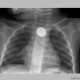

Подросток по имени Шивам Шарма на протяжении восьми лет был вынужден питаться только жидкой пищей и помалкивать. Случились такие перемена диеты и немота после того, как юный индиец упал с крыши дома. Чудом остался жив, …